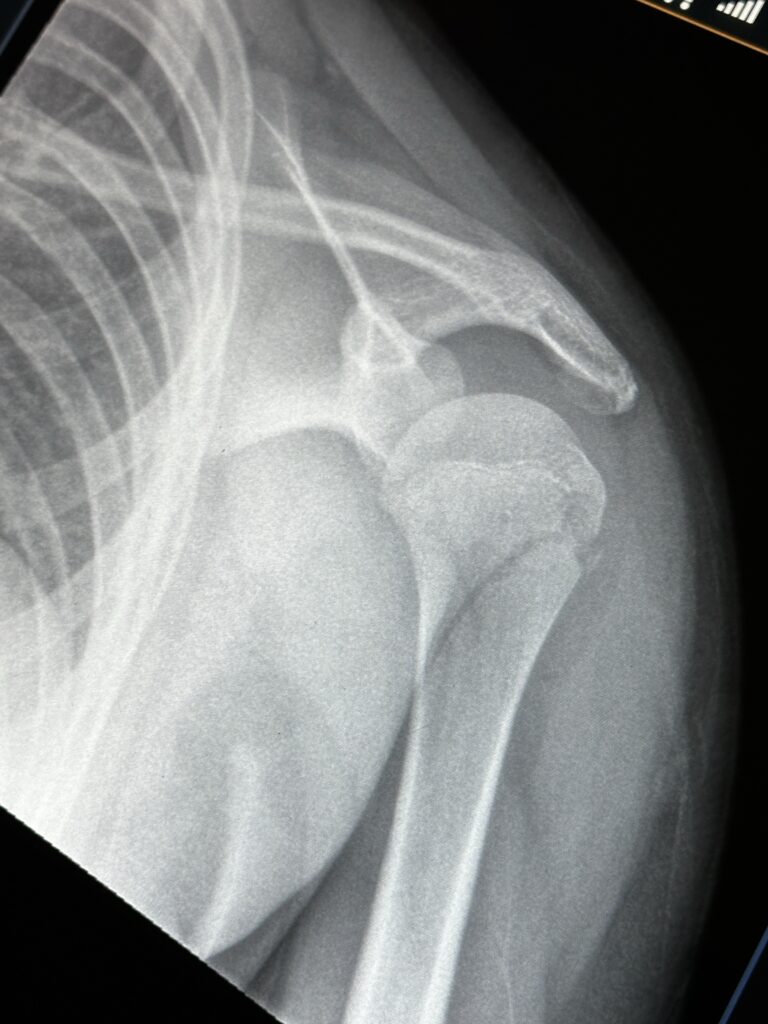

For the last few days, the boys and I were in Tennessee, on vacation with my entire family. We all had a really good time but two days before we were supposed to leave to come home, Emmett broke his arm in a tubing accident. I posted the video below on IG briefly explaining what happened.

Emmett’s okay and managed to avoid surgery. I felt it was best to get him home ASAP, so we left a day early. Emmett and I made a few stops on the way home. Elliott and Gavin stayed an extra day and are coming home with my parents. I miss my boys but I also cherished the time with Emmett.